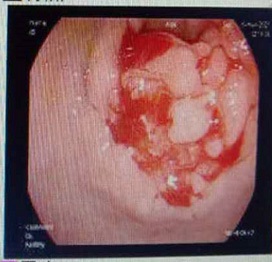

The patient, a 55-year-old male, was admitted to the hospital on March 11, 2021 due to “upper abdominal distension, pain and discomfort for more than 1 year, and recurrence for more than 2 months”. More than 1 year ago, the patient had no obvious inducement of upper abdominal distension, pain and discomfort, no acid reflux, heartburn, no nausea, vomiting, no hemesis, melena, no chest pain, chest tightness and other discomfort, no care, no diagnosis and treatment. Before 2 months, the patient’s symptoms were aggravated again, and the symptoms continued to be not relieved, so the emergency department was admitted to our hospital as “abdominal distension cause check”. Previous healthy, smoking and drinking history, no similar patients in the family. Improve relevant examinations after admission, such as: Infectious disease screening: hepatitis B surface antigen (gold standard method) positive (+), HBVDNA: 3.89 x 106 IU/ml, TAP: 128.03 um², liver function:TP: 50.23 g/L ALB: 27.8 g/L, TBIL: 34.8 g/L, DBIL: 15.00 g/L, IBIL: 19.8 g/L, ALT: 27 g/L, AST: 51 g/L, PCHE: 1879 g/L, AFP: 203.8 ng/ml, Color Doppler ultrasonography of chest and abdomen showed that liver cirrhosis was possible, portal vein velocity decreased, liver disease gallbladder, splenomegaly and splenic vein dilation. 256 row chest and upper abdomen CT (plain scan + enhanced): 1. Ground glass shadow of left lung, follow-up and reexamination are recommended; 2. Liver cirrhosis, splenomegaly, esophagogastric fundus and splenic collateral circulation; The abnormal enhancement focus in the right lobe of the liver, considering the high possibility of liver cancer, the remaining small nodule like enhancement in the liver, considering intrahepatic metastasis (Figure 1). 3. Gastric antrum space occupying, considering malignancy, please combine clinical and pathological findings. 3.0 Mr upper abdomen (plain scan + enhancement): 1. Liver cirrhosis with regenerative nodules, splenomegaly, portal hypertension, ascites and collateral circulation; 2. Abnormal signal of right posterior lobe of liver (Figure 2). Considering malignancy, please combine clinical and AFP examination. Gastroscopy showed: 1. Esophageal gastric fundus varices (severe); 2. Gastric antrum space occupying: Ca? (Figure 3); Gastric antrum pathology (HE staining Figure 4) results: (gastric antrum) adenocarcinoma. Liver puncture pathology (immunohistochemical (Figure 5) diagnosis: (liver puncture) combined with immunohistochemical results, it is consistent with hepatocellular carcinoma. Immunohistochemistry: CerbB2 (0), CK (+), HEPA (partial +), glypican (+), CD (small amount +), CD34 (blood sinus +), CK7 (-), CK8 (+), CK19 (-), CDX2 (-), Ki67 (50% +), GS (+), CK20 (-). Physical examination: Body temperature was 37OC, pulse was 78 beats/ min, respiration was 20 beats/min, blood pressure was 120/70 MHg, skin and mucosa of the whole body were mildly yellow, no rash, bleeding spots, liver palm or spider nevus, superficial lymph nodes were not touched and enlarged, and no obvious abnormalities were found in head, neck, heart and lungs during physical examination. Abdominal distention, soft abdomen, no obvious tenderness, rebound pain and muscle tension in the abdomen, liver, spleen and ribs are not touched, negative mobility dullness, bowel sounds are normal. The patient refused interventional therapy, asked for oral chemotherapy and was discharged after her symptoms improved.

Figure 3: Results of gastroscopy (Gastric antrum placeholder).